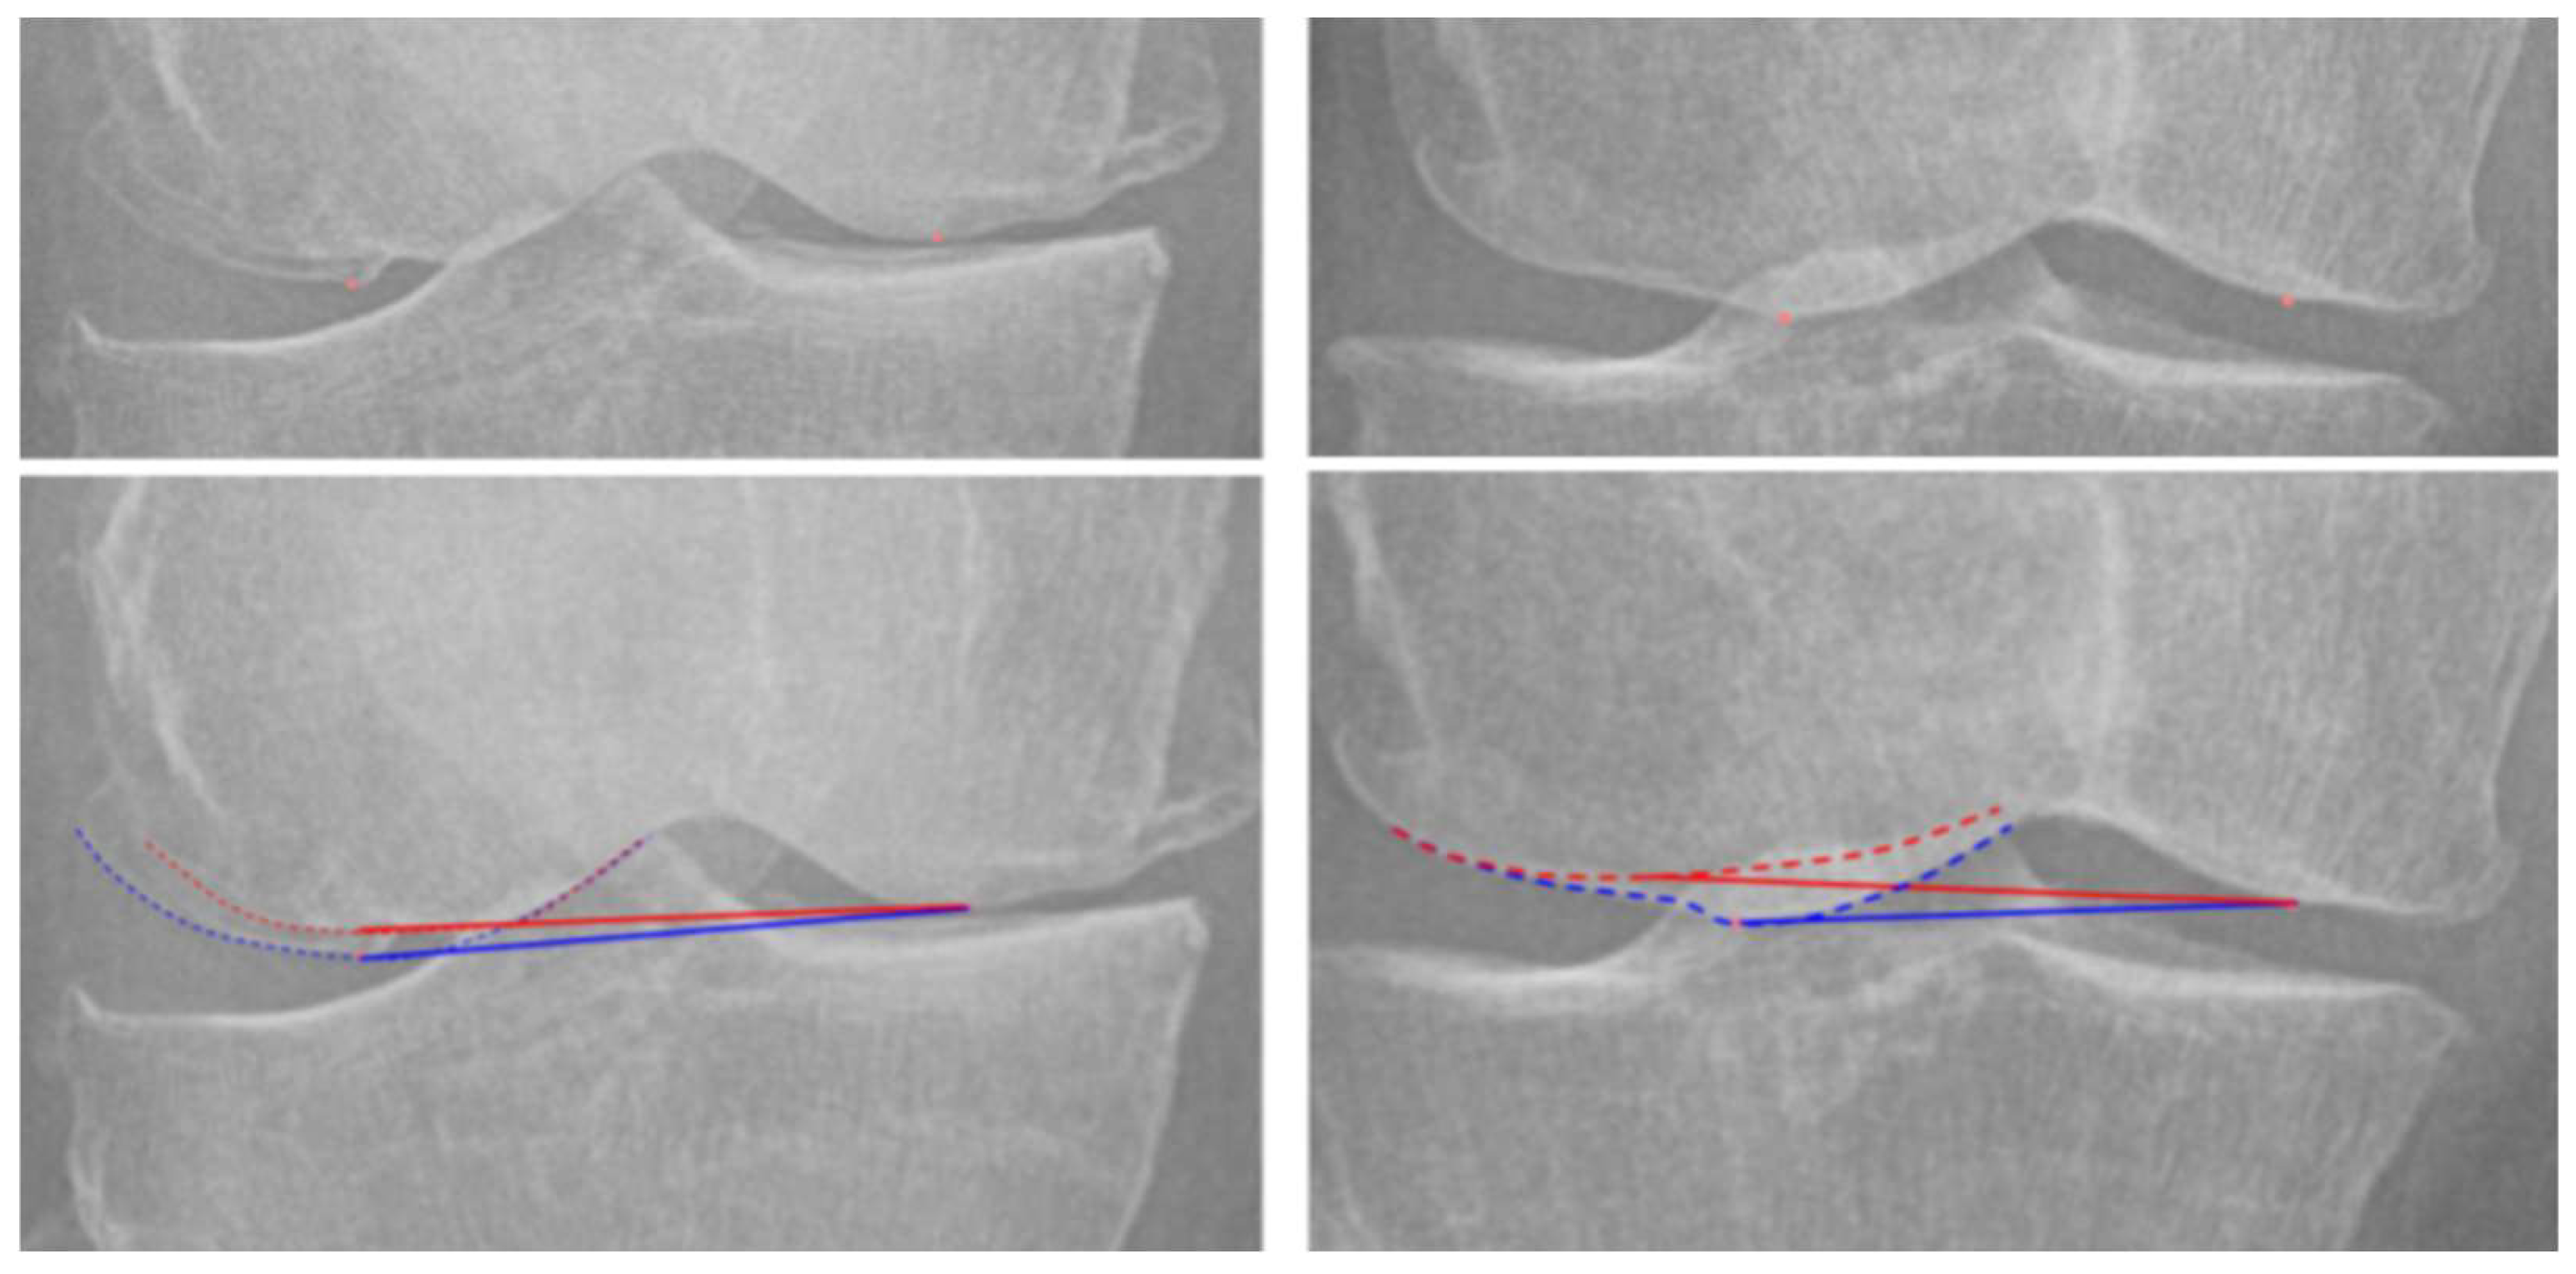

2.3. Landmark Definition and Measurement

| FNPR | femoral notch projection ratio index |

| PPR | patellar projection ratio index |